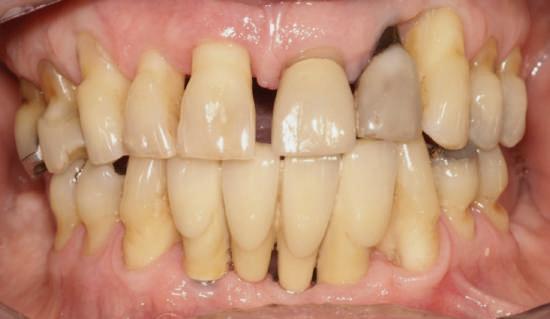

Cazul (3)

Refrezarea bonturilor individualizate

Pacientul prezenta dentiţie maxilară şi mandibulară eşuată datorită cariei secundare provocată de xerostomia post-iradiere. Pacientul suferise o disecţie cervicală radicală pentru înlăturarea carcinomului cu celule scuamoase la nivelul gâtului cu 9 ani înainte, urmată de radioterapie dar fără limită de ecranare. S-a utilizat o abordare stadializată pentru a evita protezele mobilizabile pe ţesuturile moi, extrem de uscate. Pacientul a optat pentru tratarea prioritară la nivel mandibular.

Fig. 9 prezintă bonturile de vindecare adiacente dinţilor naturali menţinuţi temporar, iar fig. 10 bonturile individualizate din prima etapă, inserate cu un contur gingival relativ bun şi fără recesie. Recesia era clar vizibilă în jurul tuturor bonturilor din prima etapă, după extracţiile adiacente şi plasarea implanturilor din a doua etapă (fig. 11). Atitudine: S-a decis îndepărtarea acestor bonturi şi amprenta corpului implantar al tuturor implanturilor astfel încât bonturile noi şi cele din prima etapă să fie frezate împreună pentru paralelism şi poziţionarea adecvată a marginii gingivale. Întrucât aceasta necesita îndepărtarea bonturilor din prima etapă care menţineau proteza provizorie, înainte de îndepărtarea tuturor bonturilor individualizate s-au plasat bonturi provizorii, cu scopul de a asigura poziţionarea adecvată şi dimensiunea verticală a restaurării provizorii. Aceste bonturi provizorii au menţinut apoi restaurarea temporară,

Cazul (3): Refrezarea bonturilor individualizate

Figurile

9. Bonturile de vindecare.

10. Bonturile individualizate în prima etapă.

11. Recesia evidentă în jurul bonturilor din prima etapă, după extracţiile adiacente şi inserarea implanturilor din faza a doua.

12. Bonturile refrezate şi noile bonturi individualizate.

în timp ce toate bonturile individualizate au fost fabricate şi/sau frezate în laborator. Fig. 12 prezintă plasarea bonturilor refrezate (la implanturile din prima etapă) şi bonturile individualizate noi (la cele din a doua etapă).